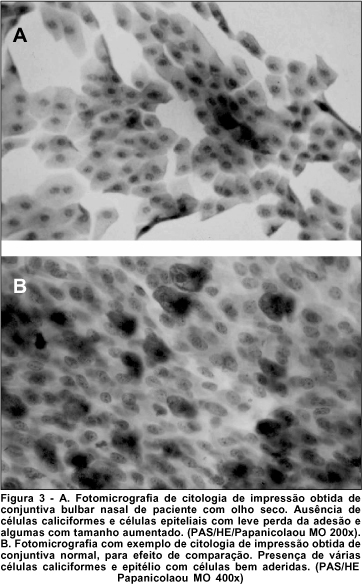

O ácido periódico de Schiff (PAS) corou as células caliciformes da conjuntiva de róseo, o que possibilitou identificar seu núcleo acêntrico e seu grande tamanho. As células epiteliais da conjuntiva são menores, com núcleo basofílico e coram-se em roxo devido à hematoxilina.

Sob microscopia óptica e com aumentos variados, analisou-se cada lâmina quanto à presença ou ausência de células caliciformes, e morfologia de células epiteliais. A amostra ideal, considerando-se que houve boa colheita e coloração padronizada, apresentou um número adequado de células morfologicamente bem preservadas, o que permitiu se observar, à microscopia óptica, a anatomia das células relativas à área desejada. (Figuras 3 e 4).